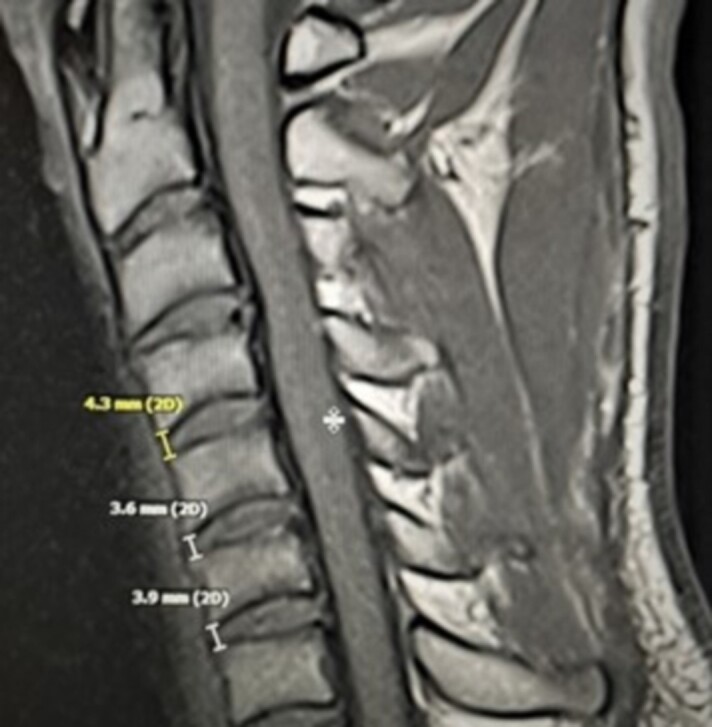

Purpose: To determine reliability and validity of musculoskeletal ultrasound (MSU) as a tool to measure cervical IVD height compared to magnetic resonance imaging (MRI) at C4-5, C5-6 and C6-7 spinal segments.

Methods: This three-phase study enrolled 40 participants. Over the course of the study, 900 measurements of IVD were taken. Ten subjects participated in cervical spine MRI and MSU imaging to determine inter-rater reliability for cervical IVD height measurements. Twenty subjects underwent MRI and MSU to obtain images for measurement comparison and Bland-Altman Analysis assessed agreement between MSU and MRI (α=.05) for validity. Randomized, blinded, repeated-measures design using mean values was used to determine inter-rater reliability with intraclass correlation coefficient (ICC(2,3)) and standard error of measurement (SEM) at each IVD segment.

Results: Anterior cervical IVD height of MRI and MSU were ≥0.91(95%CI=0.66-0.98) and ≥0.68(95%CI=0.27-0.92), respectively. Musculoskeletal ultrasound measurement's SEM between raters was comparable to MRI at ≤0.43mm (7.9%). No significant differences nor proportional bias between MRI and MSU measurements (p<0.05) were found at any IVD spinal level, r(18)=0.83, p<0.01. Average underestimation of MSU measurements compared to MRI was ≤ -0.10mm (2.2%).